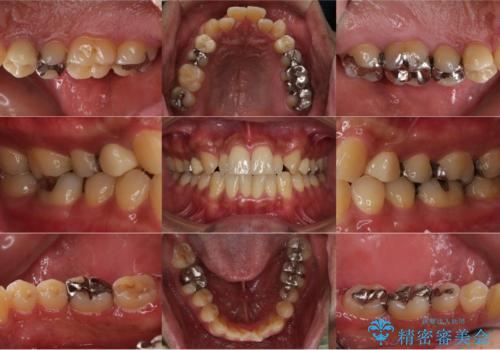

- お口の中にある銀歯を無くしたいとご相談にいらした方です。

適合の良いセラミックにてやり替えを行いました。

元々噛む力が強く、日常的に歯ぎしりもされるとの事でしたので、歯が割れてしまうリスクを軽減させるため、歯全体を覆うクラウンをメインに補綴治療を行いました。

矯正治療もご提案しましたが、ご希望されなかったため、今回は被せ物のやり替えのみ行っております。